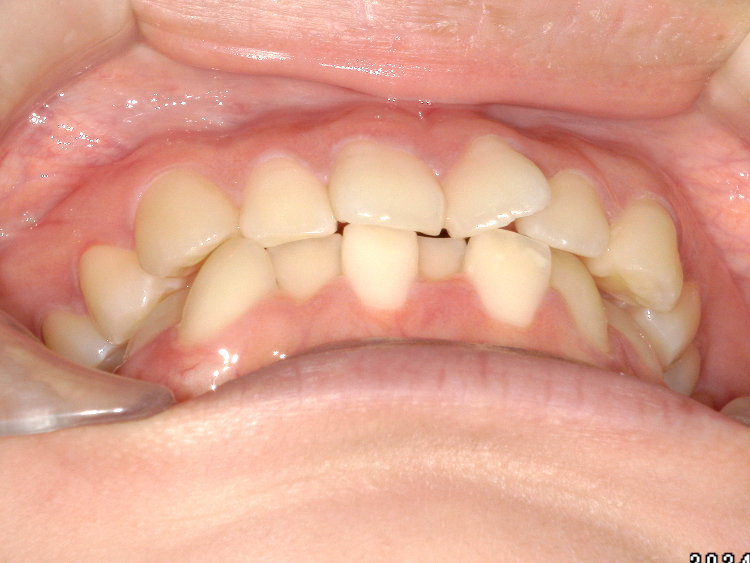

症例4

Before

After

| 主訴 | 上下前歯のがたつき |

|---|---|

| 年齢 | --- |

| 治療 期間 |

約9ヶ月 |

| 治療 内容 |

インビザラインiGoで上下顎の治療。 |

| 治療費 | ¥550,000(税込)/調整料含む |

| 治療のリスク | 矯正終了後は、リテーナーを指示通りに使用し、歯の後戻りを防ぐ必要があります。 |